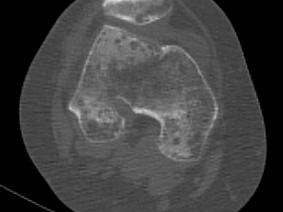

L’imagerie vient renforcer le diagnostic : la scintigraphie osseuse montre classiquement une hyperfixation dans la phase osseuse, tandis que l’IRM peut révéler un œdème médullaire, une déminéralisation mouchetée et des signes inflammatoires périarticulaires. Ces examens permettent de confirmer le diagnostic en cas de doute clinique ou d’évolution atypique.